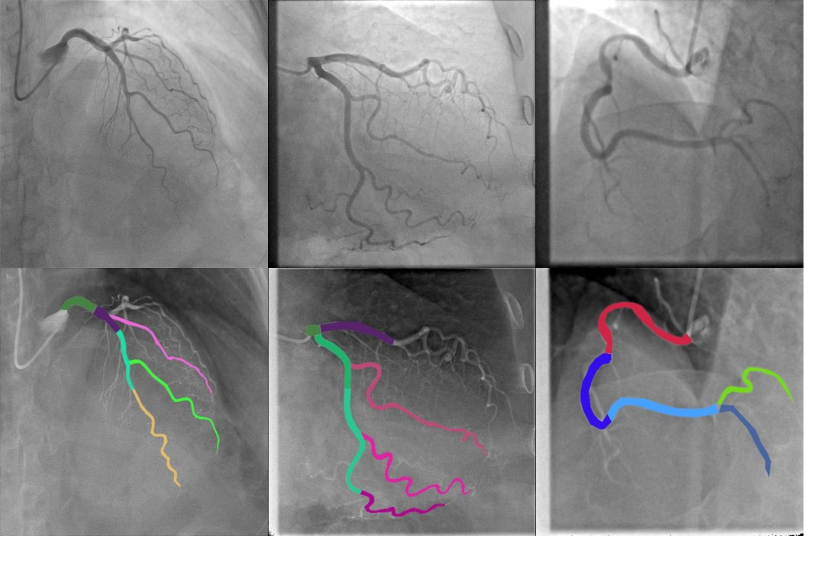

Refer to caption

Figure 2: Segmentation of vessel into specific regions according to the Syntax Score. Top row represents sample angiographic images. Bottom row represents their division into regions according to Syntax Score guidelines. To the best of our knowledge, there is no publicly available model for multi class segmentation of vessel regions.